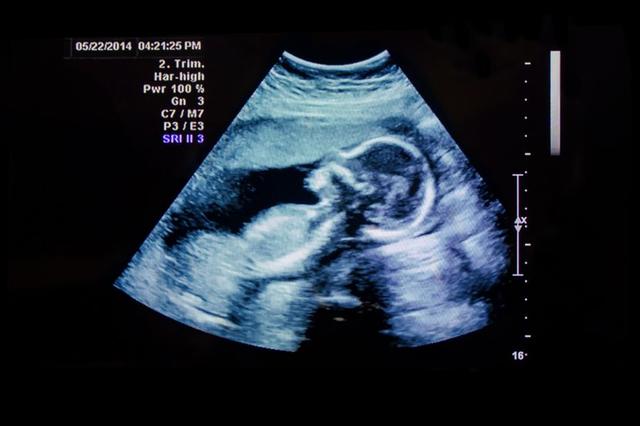

Ultraschall bezeichnet also Schallwellen mit einer Frequenz oberhalb der Hörschwelle. Diese Schallwellen werden von einem Gerät erzeugt und durch Gewebe im Körper gesendet. Die reflektierten Schallwellen werden dann vom Gerät aufgefangen und in ein Bild umgewandelt, das auf einem Monitor angezeigt wird. Dieses Bild nennt man Ultraschallbild.

Auf einem Ultraschallbild können verschiedene Gewebearten unterschiedlich dargestellt werden. Flüssigkeitsgefüllte Körperhohlräume lassen den Ultraschall vollständig passieren und erscheinen daher schwarz auf dem Bild. Knochen hingegen reflektieren den Schall komplett und lassen ihn nicht durch, wodurch sie als weiße Anteile im Bild erscheinen. Andere Gewebearten stellen sich in unterschiedlichen Graustufen dar, je nach ihrer Dichte.

Auf einem Ultraschallbild werden verschiedene Gewebe und Strukturen unterschiedlich dargestellt. Flüssigkeitsgefüllte Hohlräume wie zum Beispiel Zysten oder Blutgefäße erscheinen schwarz auf dem Bild, da der Ultraschall durch sie hindurchgelangen kann.

Knochen hingegen reflektieren den Schall vollständig und lassen ihn nicht durch. Daher erscheinen Knochen als weiße Anteile auf dem Bild. Hinter den Knochen sind keine weiteren Strukturen sichtbar, da der Schall komplett zurückgeworfen wird.

Die anderen Gewebearten, die zwischen Flüssigkeit und Knochen liegen, werden auf dem Ultraschallbild in verschiedenen Graustufen dargestellt. Dies ermöglicht es dem erfahrenen Untersucher, Gewebe mit unterschiedlicher Schalldichte voneinander abzugrenzen und Abweichungen zu erkennen.